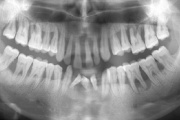

Agressiivne parodontiit

Seda parodontiidi vormi esineb umbes1%-l elanikkonnast. On haiguse kiiresti progresseeruv vorm, mille puhul patsiendid kaotavad kõik hambad enne30-35. eluaastat. Tavaliselt haigestutakse piimahammaste lõikumise ja puberteedi vahele jääval perioodil. Jagunemine:- lokaliseeritud agressiivne vorm- Loe edasi »